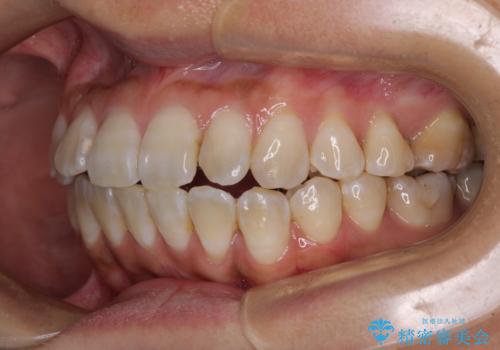

全く目立たないワイヤー矯正 上下裏側矯正

- 上下の前歯のでこぼこを気にして来院された患者様です。

職場の都合により、表側のワイヤー装置や着脱作業が頻繁なマウスピース矯正は困難とのことで、全く目立たない裏側矯正装置を用いて口元を整えることとしました。

途中転勤や出産があり、通院できない期間が長くありましたが、無事に歯列を整えることができました。